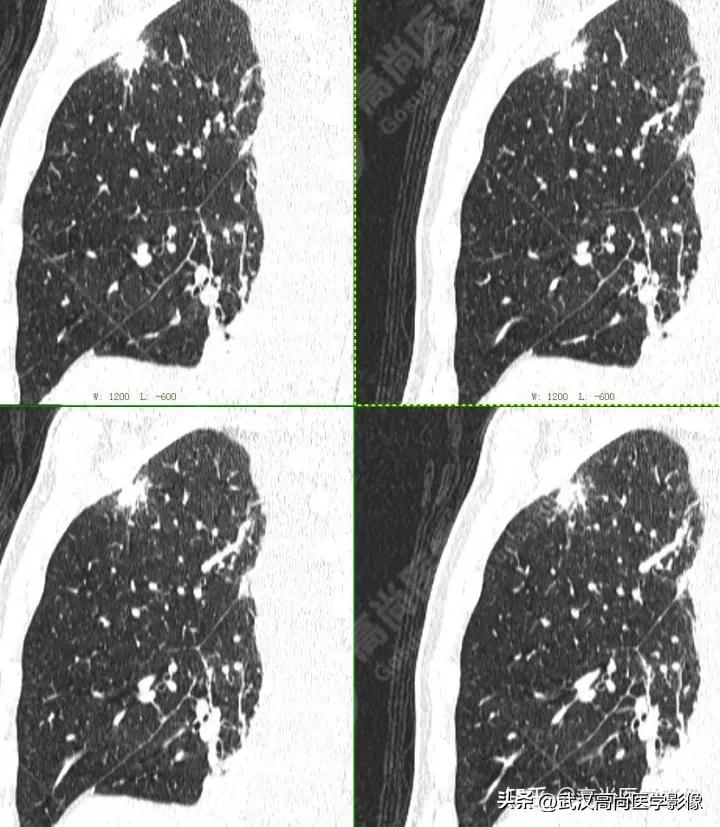

右肺上叶尖段胸膜下见一实性结节,范围约1.6cm×1.3cm,病灶紧贴邻近胸膜,伴牵拉增厚,FDG高摄取,SUVmax为7.5。

恶性CT征象:

结节边缘不光整,分叶、长短不一的毛刺,邻近胸膜牵拉明显。